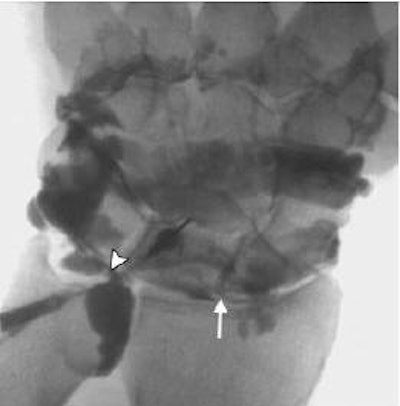

![]() |

| Above, posteroanterior radiograph of wrist in neutral position shows no evidence of scapholunate dissociation or carpal instability; alignment of both carpal rows is preserved. Below, conventional midcarpal arthrographic image of same wrist shows SLL (arrow) and central TFC (arrowhead) tears. |

| Coronal 3D dual-echo steady-state MR image (60/10, 20˚ flip angle) findings in same wrist (as above) confirm presence of volar SLL (arrow) and central TFC (arrowhead) tears. "Association Between Extrinsic and Intrinsic Carpal Ligament Injuries at MR Arthrography and Carpal Instability at Radiography: Initial Observations," Theumann NH, et al. Radiology 2006;238:950-957. |